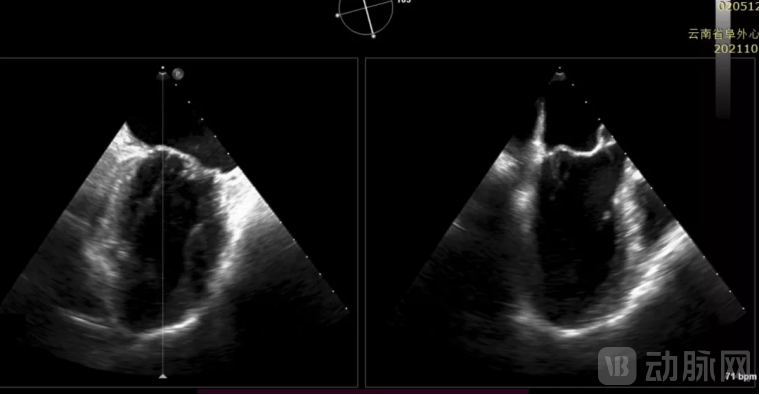

患者为年愈6旬老年男性,因反复心累气紧入院,伴双下肢进行性水肿,入院诊断:二尖瓣重度关闭不全,心功能III级,合并心房颤动,甲状腺功能减退,严重的慢性阻塞性肺部疾病等并发症。心超提示:左心房增大,左心室增大,心功能降低,肺动脉高压,瓣环扩张,前后瓣叶脱垂,二尖瓣复合病变(FMR合并DMR)。

(术中TEE见左心增大,收缩期瓣叶广泛脱垂,心功能降低)